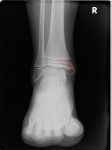

Пол пациента: Мужской пол Тип патологии: Травма Область исследования: Скелетно-мышечная система Методы исследования: Rg Мальчик 9 лет упал с самоката 3 недели назад. Жалобы на болезненность в голеностопном суставе. Ходить может, но испытывает дискомфорт. рентгенография правого голеностопного сустава в двух проекциях 21-06 рентгенограммы правого голеностопного сустава в двух проекциях ID:92476 Цель публикации: Консультация Wed, 21/06/2023 - 15:42 #1 Анастасия33 Offline Last seen: 2 years 4 months ago Joined: 23.12.2016 - 19:21 Posts: 91 вопросы к медиальной лодыжке Wed, 21/06/2023 - 16:16 #2 NIL Offline Last seen: 3 days 17 hours ago Joined: 25.11.2013 - 20:50 Posts: 18208 Анастасия33 wrote: вопросы к медиальной лодыжке За краевой перелом. При апофизе контуры более чёткие и гладкие. Впрочем,могу быть не права. Можно сравнить с противополижным суставом. "Слушай всех, прислушивайся к немногим, решай сам".© Wed, 21/06/2023 - 16:26 #3 Анастасия33 Offline Last seen: 2 years 4 months ago Joined: 23.12.2016 - 19:21 Posts: 91 Где желтым место обведено меня тоже смутило. Не вижу только сам апофиз или отломок. Но меня ещё место смутило, которое красным обвела. Тут как Вы думаете есть ли в нём травматические изменения? Приложения: Wed, 21/06/2023 - 17:53 #4 NIL Offline Last seen: 3 days 17 hours ago Joined: 25.11.2013 - 20:50 Posts: 18208 Анастасия33 wrote: Где желтым место обведено меня тоже смутило. Не вижу только сам апофиз или отломок. Меня тоже Анастасия33 wrote: Но меня ещё место смутило, которое красным обвела. Тут как Вы думаете есть ли в нём травматические изменения? Это ростковая пластина. Она не строго горизонтальна. Может выглядеть и так. "Слушай всех, прислушивайся к немногим, решай сам".© Thu, 29/06/2023 - 15:44 #5 сергеев николай Offline Last seen: 2 days 2 hours ago Joined: 22.06.2016 - 18:45 Posts: 4598 [/quote]Это ростковая пластина. Она не строго горизонтальна. Может выглядеть и так. [/quote] Но может оказаться и остеоэпифезеолизом? Или при нем клиника "ярче"? Нет нет,да тоже приходится детей описывать. Всегда боюсь пропусков( Будьте осторожны со своими мыслями они начало поступков.

вопросы к медиальной лодыжке

Где желтым место обведено меня тоже смутило. Не вижу только сам апофиз или отломок. Но меня ещё место смутило, которое красным обвела. Тут как Вы думаете есть ли в нём травматические изменения?

[/quote]Это ростковая пластина. Она не строго горизонтальна. Может выглядеть и так.

Но может оказаться и остеоэпифезеолизом? Или при нем клиника "ярче"? Нет нет,да тоже приходится детей описывать. Всегда боюсь пропусков(